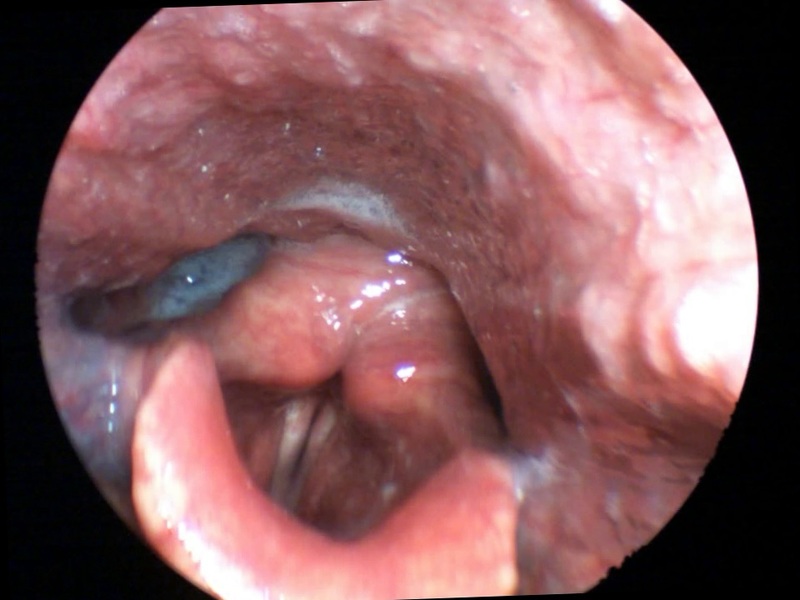

For example, in Photo A we see the specific strategy that we can use in laryngitis, an organic inflammation:

This strategy works in isolation, but also improves outcomes of other therapies in order to achieve a rapid resolution of the problem [8], because the brain reverts to recreate the best homeostasis that it knows.

In laryngitis, the induction of endogenous production of cortisol leads to an improvement in inflammation and edema, the action on the cervical sympathetic plexus improves local vascularisation, and the other points of the strategy accelerate healing, which is observed in laryngostroboscopy, as shown in Photos A1 (before the treatment) and A2 (after the treatment).